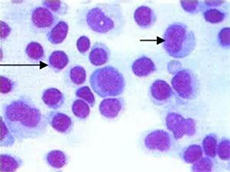

特发性血小板减少性紫癜

疾病介绍:特发性血小板减少性紫癜(ITP)亦称原发性或免疫性血小板减少性紫癜,其特点是外周血小板显著减少,骨髓巨核细胞发育成熟障碍,临床以皮肤黏膜或内脏出…【详细】